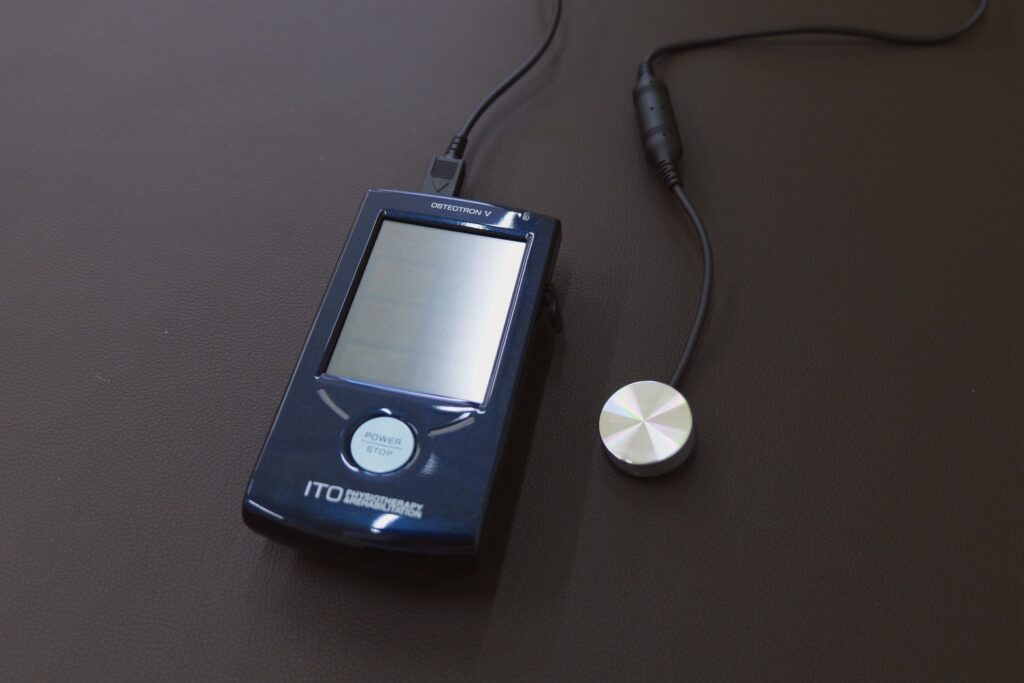

組織回復の超音波治療機器